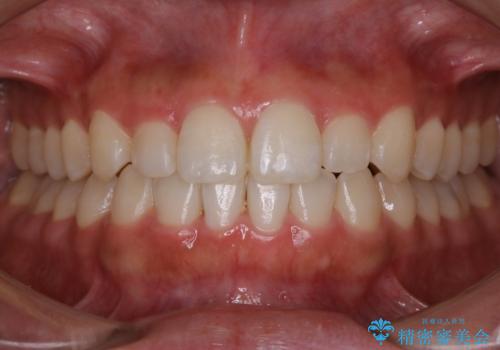

【非抜歯】前歯のガタつき マウスピースの部分矯正

- 上下の前歯の細かいガタつきの治療をご希望されて来院されました。

奥歯部分にはガタつきや噛み合わせの問題などがほとんど見られず、前歯のガタつきも軽度だったため、インビザライン ライト パッケージでの部分矯正を行うこととなりました。

今回のケースでは奥歯の噛み合わせに問題がほぼみられなかったため、前歯の位置のみに焦点を当て部分矯正を行いました。

適応されるケースが限られるものの、適応であった場合の治療期間は全体矯正と比べると格段に短くなり、費用も抑えられます。